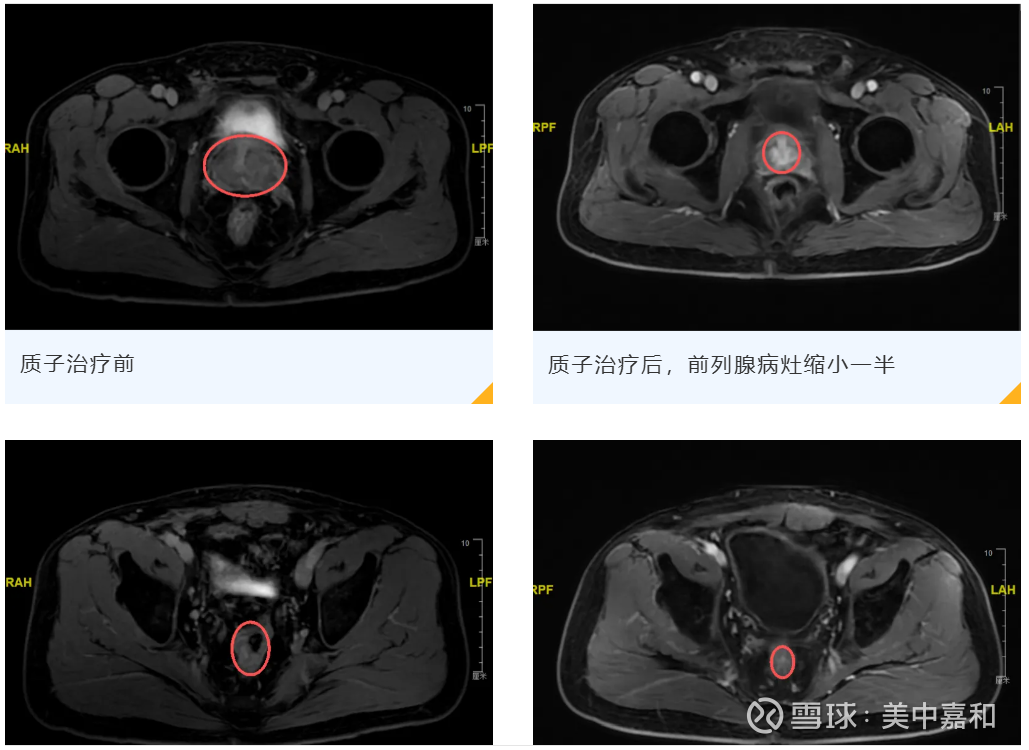

广州泰和质子治疗同步 “狙击” 双癌灶 六旬患者病灶显著缩小 彰显技术硬实力

9月12日,广州泰和肿瘤医院发布案例分享,六旬C先生确诊前列腺癌(高危局部进展型,侵犯精囊)与直-乙交界癌双原发肿瘤,因前列腺毗邻膀胱、肠道,传统放疗易损伤正常组织,遂赴广州泰和肿瘤医院寻求质子治疗。

针对盆腔双癌灶复杂情况,医院多学科团队(MDT)制定一体化方案:同步开展 “前列腺癌根治性放疗+直肠癌新辅助放疗”及化疗,依托华南首家临床应用的瓦里安ProBeam®质子系统,量身设计28次质子治疗计划。治疗后成效显著:C先生总前列腺特异性抗原(TPSA)大幅下降,前列腺及直肠的两处病灶明显缩小。

此次双癌灶治疗突破单癌种思维局限,质子治疗凭借 “精准覆盖多靶区、降低80%周围器官辐射量” 的优势,高效覆盖多个肿瘤靶区,同时显著降低对周围共用危机器官的辐射损伤,为尽可能获得根治机会及保有生活质量这一理想目标提供了关键的技术支撑,印证了广州泰和在复杂肿瘤诊疗中的技术壁垒与多学科协作能力,此举进一步巩固了其在国内外质子治疗领域的领先地位,为公司高端肿瘤诊疗业务的竞争力增添了有力支撑。